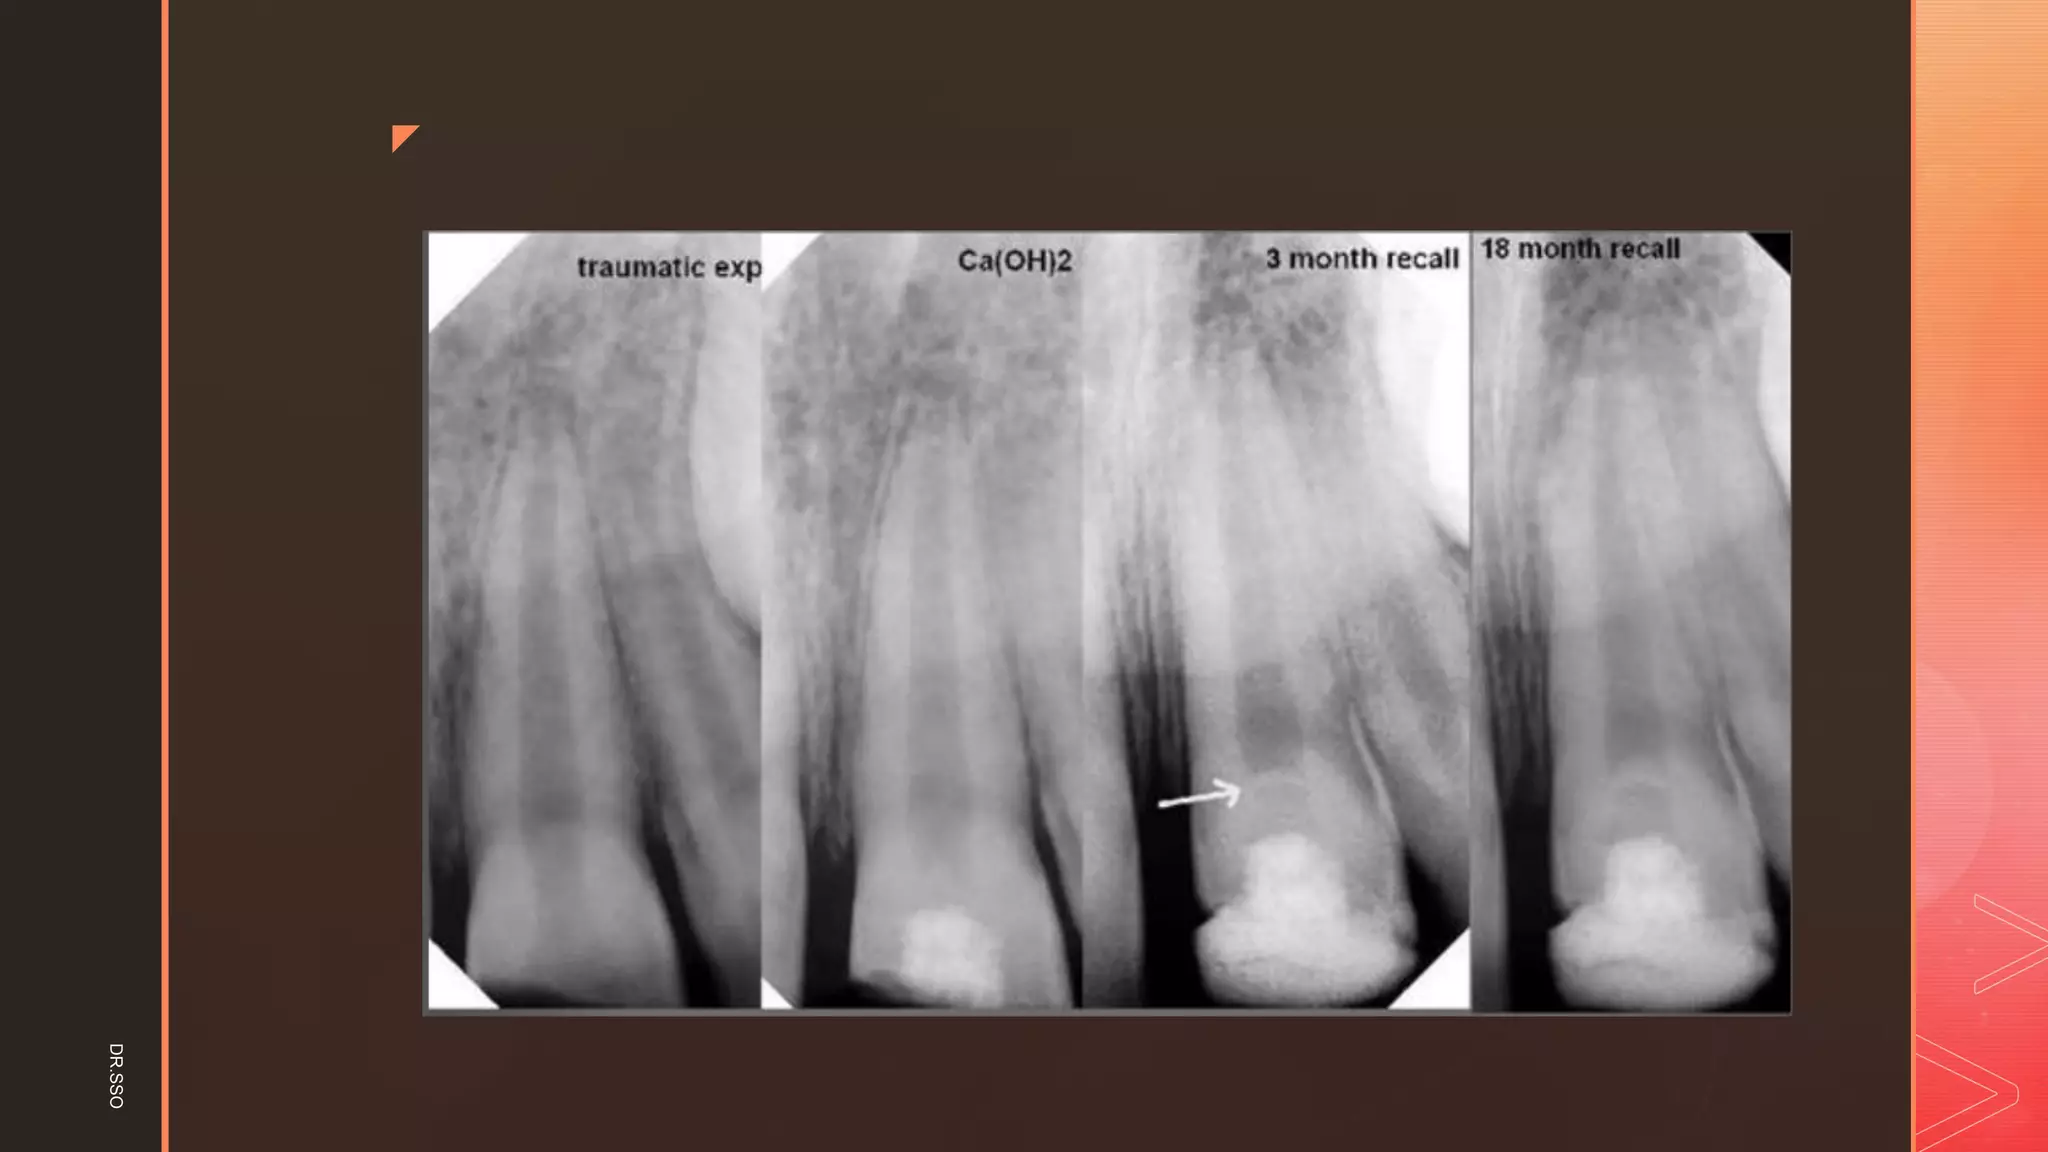

IN TEETH WITH IMMATURE APICES

Calcium hydroxide

▪ Ca(OH)2 for apexification in the pulpless tooth was first reported

by Kaiser in 1964

▪ The technique was popularised by the work of Frank in 1966